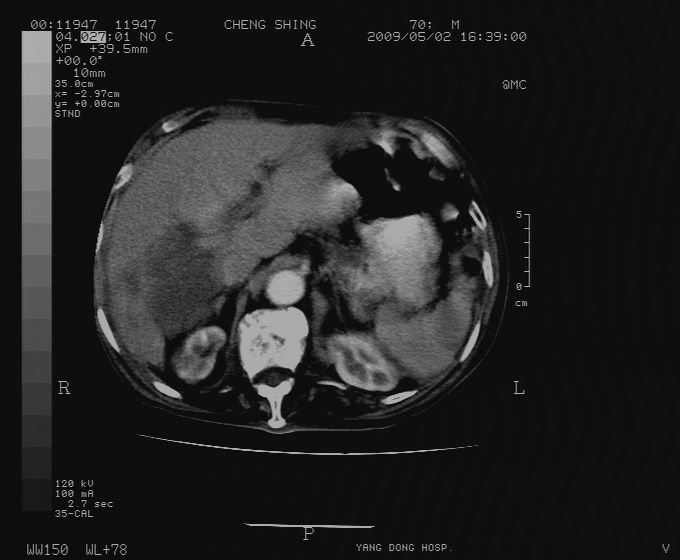

标题: CT19743:男70岁,肺部疾病入院,B超发现肝右叶占位,CT [打印本页]

标题: CT19743:男70岁,肺部疾病入院,B超发现肝右叶占位,CT

肝表面塌陷,病灶周围有子灶,前面较大子灶强化符合肝癌表现,考虑肝癌肝转移可能性大.

增强做得不好,不太好分析。

1)考虑肝癌并肝内转移。2)少量腹水。3)双侧胸腔积液。

1)考虑肝癌并肝内转移。2)少量腹水及双侧胸腔积液。3)椎体退变。